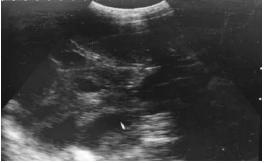

③后期B超影像图表现及其特征

妊娠后期 (配种后84 d~114 d) 胚胎生长发育迅速,该时期的影像图 (见图 3),可以清楚的看到胎儿的肋骨和脊柱,且体腔分辨清晰。

图3 妊娠95 d图像

随着妊娠天数的增加,探头的探测区域要逐渐扩大。妊娠中期,孕囊中的羊水减少,孕囊变得不规则,且胎儿骨骼逐渐发育,因此影像图谱应以观察白色强回声的骨骼 (脊柱) 图像来判断。妊娠后期应以观察胎儿脊柱胸腔的骨骼图像来判断。